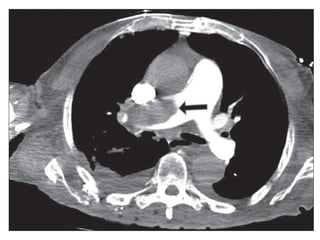

Chest x-ray

• Mostly normal findings

• Done to exclude other pathology

• Pleural effusion/ Atelectatic bands

• Specific signs:

- Hampton’s hump (in infarction)

- Westermark sign

- Palla’s sign

- Fleischner sign (in massive embolism or PHTN)